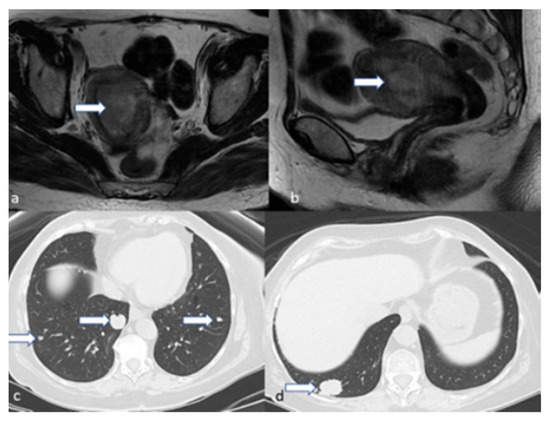

5.3. Magnetic Resonance Imaging (MRI)

4.4. Stage IV

5.2. Computed Tomography (CT)